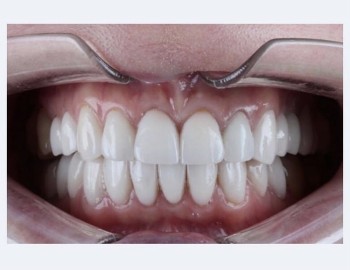

Мамедов Азад Велиевич принимает в «Центр семейной медицины ЖИВОНОСНЫЙ РОДНИК» в Белгороде. Стаж 11 лет. Специализируется на ортопедии, хирургии и имплантологии, по которым клиника оказывает 13 услуг. Имеет 3 работы до/после в портфолио. Квалификация специалиста подтверждена 10 лицензиями, сертификатами и наградами. Также 32top представляет форму онлайн расписания, через которую можно записаться к специалисту на свободную дату и время.

3 работы в портфолио